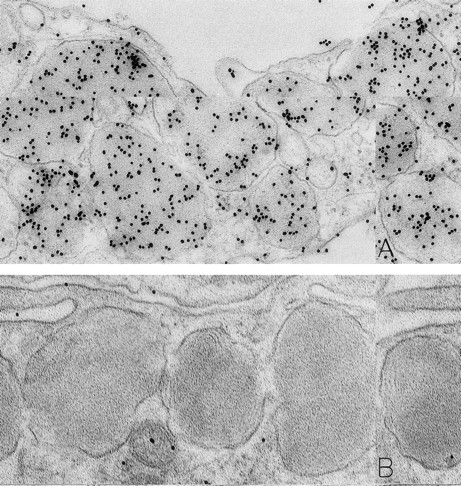

Skin biopsies from sites that had been injected with rhSCF, obtained from patients no. 2 and no. 3 who had received rhSCF for 13 days (A) or 1 day (B through D), respectively. The biopsy in (A) was obtained 1 hour 45 minutes after the SC injection of 5 μg/kg of rhSCF, whereas the biopsy in (B), (C), and (D) was obtained 1 hour 40 minutes after the SC injection of 25 μg/kg of rhSCF. A large amount of DAO-gold label is present on the electron-dense contents of cytoplasmic granules in the mast cell in (A; solid arrowhead); the cell exhibits evidence of secretory activity, and an extruded, non–membrane-bound granule with altered matrix (which is located external to the plasma membrane) retains very little DAO-gold label for histamine (open arrowhead). However, DAO-gold heavily labels adjacent collagen fibers, which are seen in cross-section (arrows). In (B), multiple extruded, membrane-free mast cell granules (G), which exhibit altered matrix materials, are present in the interstitium near the degranulating mast cell; these extruded granules exhibit relatively little DAO-gold labeling for histamine, except in regions of the granules that contain the most electron-dense matrix material (solid arrowheads). In (C), the DAO-gold was absorbed with solid-phase histamine before being used to stain the specimen. Nearly all DAO-gold staining of intracellular mast cell granules (arrowhead), as well as of the extruded, membrane-free granules (G), was abolished by this specificity control. (D) shows that the extensive fibrin deposits in the extracellular space in this biopsy are heavily labeled with DAO-gold. Original magnifications: (A) ×52,500; (B) ×28,000; (C) ×46,500; and (D) ×45,000.

Many of the dermal mast cells in the rhSCF-injected sites were undergoing secretion, as indicated by the extrusion of membrane-free, altered granules through multiple openings in the plasma membrane (Fig 2A through C). Such findings are very similar to those observed in isolated human skin mast cells that had been stimulated with anti-IgE in vitro.24 We found that the extruded, membrane-free mast cell granules persisted near mast cell surfaces, as well as enmeshed among adjacent collagen fibers, for up to 2.5 hours after rhSCF injection (the latest interval after injection that we studied). Notably, these membrane-free, swollen, rounded granules with altered matrices generally contained merely trace amounts of DAO-gold labeling for the presence of histamine (Fig 2A and B). Rarely, we observed mast cells with intracytoplasmic degranulation channels containing altered, swollen granules; these structures and the contained membrane-free granules also were generally devoid of histamine labeling. The specificity controls resulted in no gold labeling of the extruded granules, indicating that the weak level of DAO-gold labeling of these structures indeed represented residual histamine associated with the matrices of the released granules (Fig 2C).

The rhSCF-injected skin sites had extensive deposits of extracellular fibrin. Much of this fibrin was bound to interstitial collagen, whereas some fibrin deposits occurred near secretory mast cells and their extruded granules. There was striking labeling of these masses of interstitial fibrin with DAO-gold (Figs 2D and 4A). By contrast, no fibrin was detectable in the control skin biopsies. Specificity controls for the enzyme-affinity method for histamine resulted in no labeling of fibrin (Fig 4B). Bundles of extracellular interstitial collagen in rhSCF-injected sites also stained with the DAO-gold reagent (Fig 5A). Again, specificity controls resulted in no labeling of the collagen at such sites (Fig 4B). In many areas, secretory mast cells, with DAO-gold-negative, extruded, membrane-free granules attached to their surfaces, were intimately associated with gold-labeled collagen fibrils (Fig 2A). However, collagen in the basal lamina (whether present beneath the basal layer of the epidermis and skin adnexae, surrounding Schwann cells in dermal nerves, or underlying vascular endothelial cells and pericytes) did not stain with the DAO-gold enzyme-affinity method (data not shown).